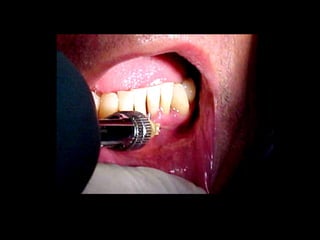

diagnóstico rápido de lesiones de la mucosa oral sospechosas de

malignidad, en la consulta odontológica. De entre los distintos métodos

propuestos: tinción con colorantes, iluminación con luz fluorescente y biopsia

optimizada con toma de muestras ("brush biopsy"), monitorizada por

computadora y valorada por un equipo específico de anátomo-patólogos,

éste último es el que más documentado y con un mayor nivel de garantía y

seguridad.

Exosten varios colorantes para detectar las lesiones malignas en la cavidad

bucal, inicialmente se utilizó el yodo tópico que está desechado por los

problemas alergénicos.

Azul de metileno

Rosa de Bengala

Cloruro de Tolonio

Sin embargo el más barato y efectivo es el Azul de Toloidina

Técnica de aplicación

1. Enjuagarse entre 1-3 veces con ácido acético al 1% durante 30 segundos.

2. Enjuagarse con azul de toluidina al 1% durante 1 minuto

3. Volver a enjuagarse con ácido acéticoal 1% durante 30 segundos.

La coloración orienta, nunca sustituye el criterio del cirujano.